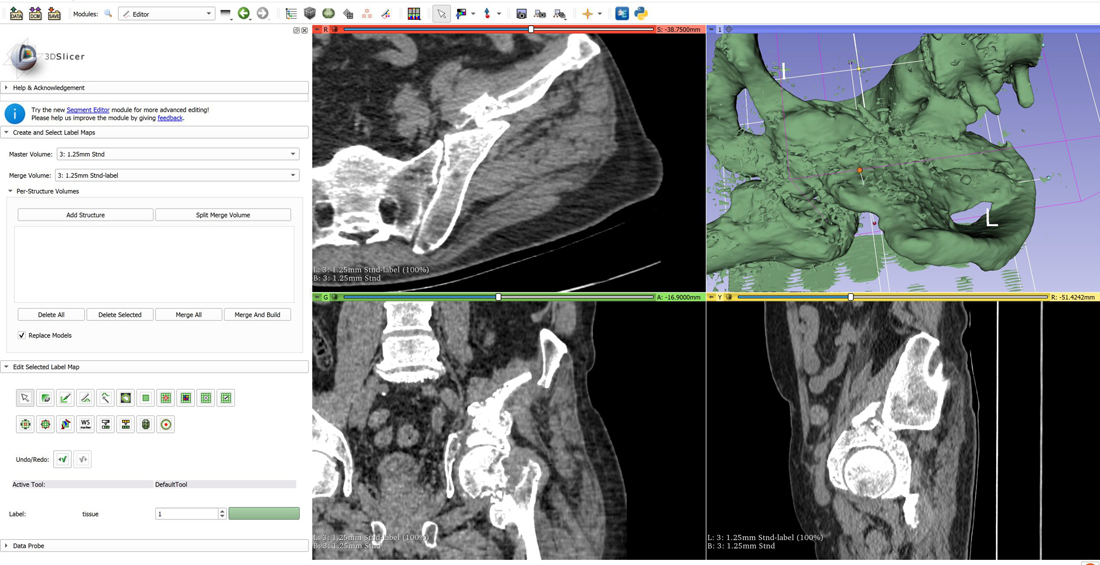

По его словам, в лабораторию «ФабЛаб» уже обратились травматологи из симферопольской больницы. К ним поступил пациент, который после ДТП долго лежал в реанимации. В результате переломы костей таза срослись неправильно, и теперь, когда стала возможной операция, врачи хотят максимально к ней подготовиться. Специалисты лаборатории с помощью специального программного обеспечения сделали реконструкцию 3D-модели тазовой кости по КТ-снимкам и распечатали её с размерами, точно соответствующими оригиналу.